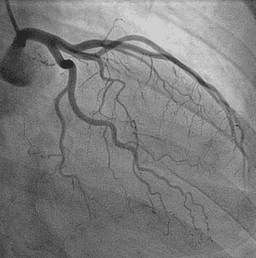

Working with MIRACL.ai means partnering with a leading academic Core Lab in multimodal cardiovascular imaging, at the heart of a clinical, scientific and technological environment of excellence.

MIRACL.ai supports you throughout the lifecycle of your projects, from data to scientific valorization, according to recognized methodological, regulatory and academic standards.

Expert and standardized centralized review

Image analysis by specialized readers following validated protocols, with divergence management, traceability and quality control.

Producing reliable ground truths

Annotations, segmentations, scorings and imaging variable extractions used as references for clinical research and algorithm development.